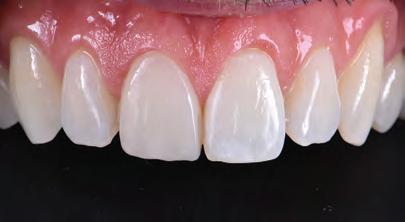

A 30-year-old patient, with a negative medical history, came to the clinic requesting the replacement of the previous composite reconstruction performed 10 years earlier following a trauma to UR1.

On clinical examination, UR1 was responsive to viability testing, and did not present periapical lesions on the radiograph performed on the same day (Figure 1). UR1 was discoloured and in a more palatal position than the contralateral central UL1 (Figure 2). The aesthetic analysis highlighted an asymmetry of the gingival zenith between UR1 and UL1. Through the use of a periodontal probe, after plexus anaesthesia, the altered passive eruption of the type IA junctional epithelium was confirmed according to the classification of Coslet et al. (Figure 3).

FIGURE 1: Radiograph without periapical lesion.

The finishing and polishing procedures were carried out trying to emulate the transition lines of UL1 (Figures 12 and 13).

The patient was checked again after 21 days (Figures 14 and 15) and 12 months (Figure 16) to evaluate the aesthetic result in shape and colour.

FIGURE 16: Restoration after 12 months.